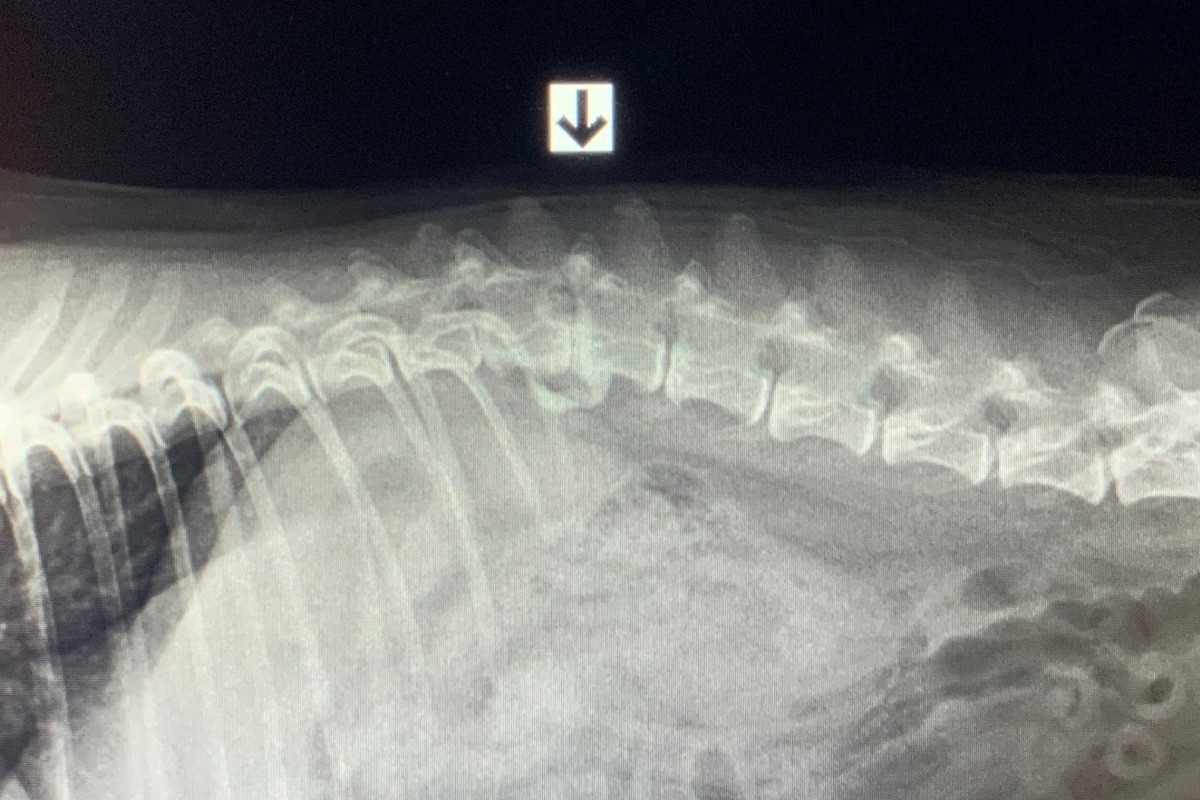

During Ninja's examination, x-rays confirmed a bulging/ruptured disc. The L1-L2 disc space is collapsed with bridging spondylosis (arthritis) underneath. There appears to be mineralized material overlying this disc space. The disc space in front and behind this area also look narrowed.

We are currently treating her with acupuncture, multiple medications for pain and muscle relaxation, and strict rest. The appearance of the x-rays are concerning that there is a lot of spinal cord compression, so medical management will end up being a temporary band-aid at best.